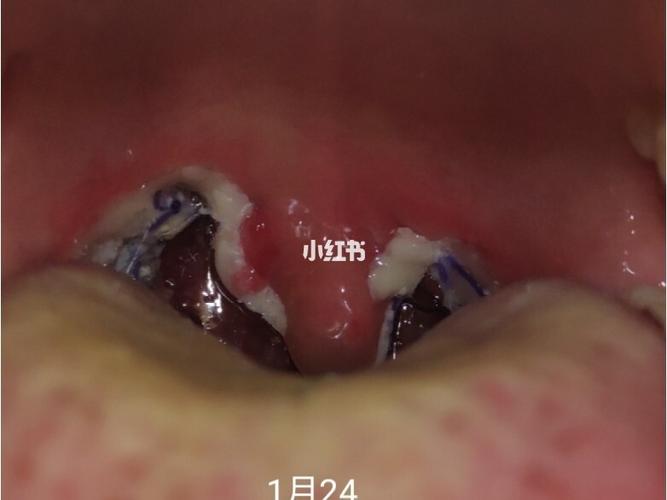

扁桃体术后白膜脱落过程图

扁桃体术后白膜

扁桃体术后图片

扁桃体术后恢复照片

扁桃体术后感染图片

扁桃体术后恢复过程图

扁桃体手术后感染图片

扁桃体手术伤口白膜图

扁桃体手术伤口恢复图